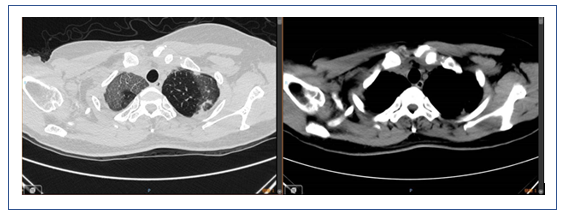

此例患者为起病急骤,病程较短,无基础疾病,胸部CT显示弥漫性磨玻璃影,结合其临床表现和实验室检查结果,主要考虑是否与病毒感染相关。另外,患者痰中带血丝,但病毒学检查为阴性,建议尽早行支气管肺泡灌洗。在治疗方面应以抗病毒为主,如果患者呼吸困难比较严重,可以适当加用一些激素。

该患者急性起病,发热,痰中带血,病情较重,但影像学改变并不典型。患者胸部CT示双肺磨玻璃影,双下肺可以见与支气管伴行的肺血管明显增粗,右下肺可见血管影扩张,中叶胸膜下片状高密度影,左下肺血管影扩张较明显。目前在诊断方面考虑感染性病变和非感染性病变。非感染性病变主要考虑两类,一类是非肿瘤相关疾病,如自身免疫性疾病,另一类是肿瘤相关病变,如淋巴瘤、血液系统疾病等。结合患者的临床表现和检查结果,我个人认为非感染性疾病的可能性较大,仍需进一步检查明确,如支气管肺泡灌洗、肺活检等。